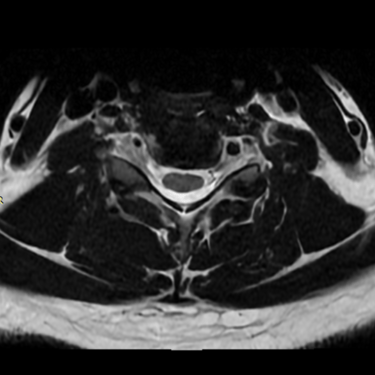

Discopatía Cervical con Inestabilidad de Columna | Diagnóstico por Resonancia Magnética

La discopatía cervical con inestabilidad de columna es una patología que compromete la movilidad y estabilidad de la región cervical, generando síntomas como dolor cervical crónico, rigidez, irradiación a miembros superiores y, en casos avanzados, déficit neurológico. La resonancia magnética (RMN) es el método diagnóstico de elección, ya que permite evaluar la degeneración discal, protrusiones o hernias discales, cambios en los cuerpos vertebrales, compresión radicular y signos de inestabilidad. Su precisión ayuda a planificar el tratamiento más adecuado, que puede incluir manejo conservador o cirugía, según la gravedad y el compromiso neurológico del paciente.